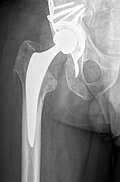

Oberschenkelamputation nach periprothetischer Tibiafraktur bei nicht sanierter periprothetischer Kniegelenksinfektion

Kurze Vorgeschichte: Herr S, ein 67-jähriger Patient, erhielt 2011 (Abbildung 1) bei ausgeprägter Gonarthrose eine primäre KTEP rechtsseitig. Im weiteren Verlauf zog er sich 2017 eine periprothetische Tibiafraktur zu, die mit einem Knieendoprothesenwechsel auf ein achsgeführtes Implantat (Abbildung 2) und Schaftverlängerung der Tibia im September 2017 ex domo therapiert wurde. Im Verlauf zeigten sich eine anhaltende Sekretion und eine partielle Nekrose am unteren Wundpol.

Ende Novemeber 2018 erfolgte eine erneute Wiedervorstellung des Patienten in unserer Notaufnahme. Hierbei beklagte er rezidivierende lymphödematöse Schwellungszustände des Unterschenkels rechts, Knieschmerzen und radiologisch nachgewiesene Flüssigkeitsansammlung im Kniegelenk rechts. Eine Punktion des Kniegelenkes erfolgte im Dezember 2018, wobei sich eine chronische Infektion mittels Candida parapsilosis des rechten Kniegelenkes bestätigte.

Wir haben anschließend im März 2018 den Ausbau der einliegenden Kniegelenksprothese empfohlen, um den Infekt zu sanieren. Dies wurde jedoch seitens des Patienten abgelehnt.

Im weiteren Verlauf zeigten sich die Weichteile des rechten Unterschenkels zunehmend mazeriert und belegt. Zudem sei der Patient erneut gestürzt. Eine erneut durchgeführte Röntgendiagnostik zeigte erneut eine periprothetische Tibiafraktur (Abbildung 3) bei einliegender achsgeführter KTP mit langem tibialem Stem und bekanntem periprothetischem Infekt mit Candida parapsilosis. Wir haben die Befunde ausführlich mit dem Patienten besprochen und in Zusammenschau der Befunde schließlich die Indikation zur Oberschenkelamputation gestellt.

Diese konnte komplikationslos im Mai 2018 durchgeführt werden (Abbildung 4 und 5).

Womöglich hätte der drastische Schritt einer Amputation durch eine frühzeitige Prothesensanierung, welche jedoch durch den Patienten abgelehnt wurde, verhindert werden können.